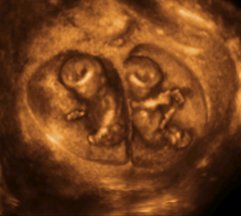

Twin Pregnancy (TWIN PREGNANCY)

TWIN BABY

Multiple pregnancies are the most common in twin pregnancies. Twin pregnancies occur in 1 of every 80 pregnancies is formed by natural means. This ratio is in the area of ​​drug treatment for pregnancy and especially in vitro fertilization increases even more work.

Gemini twins (monozygotic) and fraternal twins (dizygotic) is divided into two parts. MZ to "their (identical)," DZ to "brother (fraternal)" is given in the name. All of them are monozitotik twin one twin.

Monozygotic twins (identical twins): Here is fertilized by sperm 1 egg 1 as singleton pregnancies, but later split. Sex is always the same. Genetic makeup is the same. If this division fertilization after in the first 3 days diamniotic dichorionic (two amniotic sacs, two placenta), if 4-8 days diamniyonik monokoryotik (two amniotic sac, one placenta), no matter of 9-13 days monoamniotic monochorionic (one amniotic sac, one placenta) twins would pregnancies. The most common is seen diamniotic monokoriyoni. 13. If the result of dividing the day after Siamese twins (conjoined twins) occurs. Identical twins >>

one or two follow-up of twin pregnancy the placenta (monochorionic-dichorionics) is very important. This distinction is made for around 11-15 week ultrasound can be very useful.